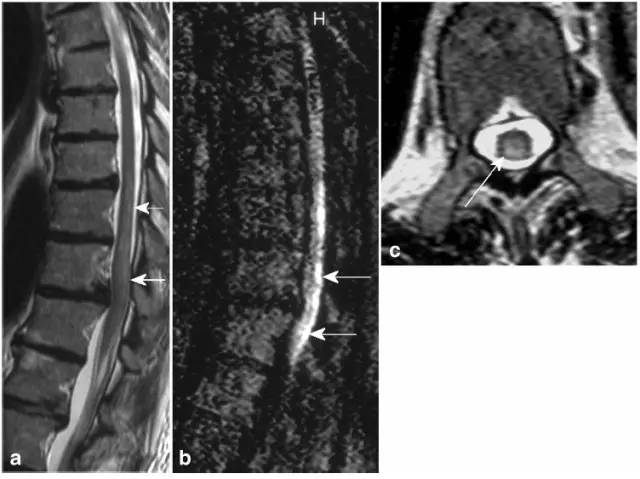

病例8:腰膨大和脊髓圆锥梗死。T2(图a矢状位,图d和e轴位)显示脊髓圆锥近完全横贯性高信号,T1可见轻微强化(图c)